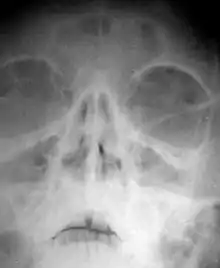

Ознаки гострого фронтиту: головний біль (переважно у лобній ділянці), біль в очах, можливі гнійні та слизові виділення, гарячка; температура переважно субфебрильна при хронічному фронтиті — тривалий стійкий нежить (виділення, головним чином, з однієї ніздрі), на рентгенівських знімках ділянка лобних пазух зі зниженою прозорістю.